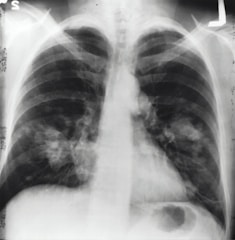

Choroby płuc

Diagnoza i leczenie astmy, POChP, przewlekłego kaszlu i infekcji

Choroby śródmiąższowe

Opieka nad pacjentami z włóknieniem płuc i sarkoidozą